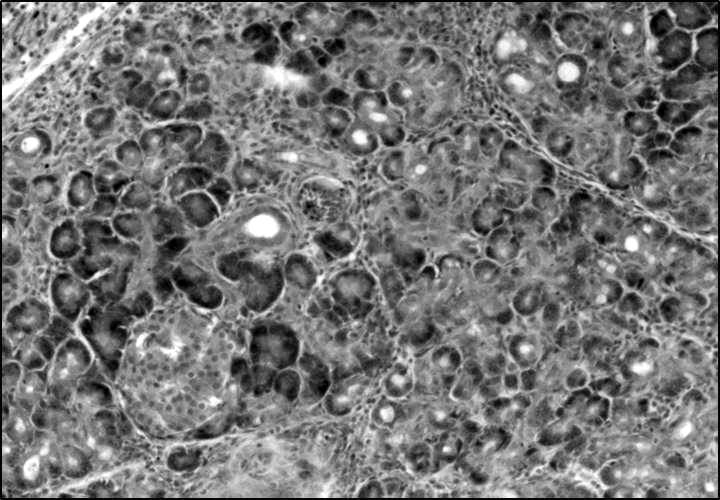

К 7-м суткам течения ОПП в контрольной группе в поджелудочной железе были расширены соединительнотканные междольковые трабекулы с признаками выраженного отека и интенсивной лейкоцитарной инфильтрацией. Ацинарные структуры экзокринной части долек железы в большинстве случаев визуализировались с признаками деструкции, сохранилась лишь малая часть экзокриноцитов (менее 30 %). Строма долек железы была инфильтрирована сегментоядерными лейкоцитами. Сохранившиеся панкреатические островки Лангерганса обнаруживались с признаками выраженного отека стромы, большинство клеток островков (более 50 %) было деструктивно изменено (рис. 1). В парапанкреатической клетчатке и висцеральной брюшине имелась интенсивная инфильтрация полиморфноядерными лейкоцитами, что свидетельствовало о развитии гнойного перитонита и гнойного парапанкреатита – флегмоны парапанкреатической клетчатки в брыжейке двенадцатиперстной кишки. Выявленные изменения соответствовали гистоморфологическим проявлениям второй фазы течения острого панкреатита с развитием гнойно-септических осложнений в виде гнойного перитонита и некротического парапанкреатита. В легких определялись сливные фокусы бронхопневмонии с поражением средних и мелких бронхов, в большинстве случаев обнаруживалось их слияние (фокусов) с развитием долевой пневмонии. В перибронхиальных сосудах в просвете отмечалось краевое стояние лейкоцитов и признаки лейкодиапедеза. В двух случаях (20 %) макроскопически выявлено осложнение пневмонии в виде эмпиемы плевры. В селезенке визуально обнаружено снижение числа лимфоидных фолликулов белой пульпы и оголение стромы органа, границы между красной и белой пульпой были стерты. В сохранившихся лимфоидных фолликулах была нарушена клеточная зональность. Данные изменения свидетельствовали о выраженной воспалительной реакции в паренхиме селезенки. В печени балочное строение органа было не изменено, но сохранялись признаки полнокровия сосудов венозного коллектора очагового характера, а в части портальных трактов перифокально обнаруживали мелкие круглоклеточные инфильтраты. В паренхиме органа определялись очаговые некрозы гепатоцитов в виде кариолизиса ядер и разрушенных клеточных мембран с круглоклеточной инфильтрацией. В части случаев (70 %) в портальных трактах обнаруживалась выраженная пролиферация протокового эпителия, множественные перипортальные некрозы и жировая дистрофия гепатоцитов, что указывало на вовлечение печени в системную воспалительную реакцию. В почках находили полнокровие сосудов, а в синусоидальных сосудах коркового вещества отмечали капилляростаз с очаговыми скоплениями лейкоцитов, что указывает на развитие острого нефрита. В сердце в миокарде желудочков выявляли признаки выраженного интерстициального отека, подэпикардиальные сосуды были полнокровны с явлениями капилляростаза. В миокарде предсердий – определялись подэпикардиальные фокусы деструкции кардиомиоцитов в виде кариопикноза ядер и распада саркоплазмы, круглоклеточная инфильтрация в зоне дистрофии кардиомиоцитов. Это позволяло говорить о наличии начальных признаков развития миокардита и перикардита, что подтверждало вовлечение сердца в системную воспалительную реакцию.

Рис. 1. Поджелудочная железа, некроз панкреатического островка, 7-е сутки, контрольная группа. Окр. гематоксилином и эозином, ув. ×200